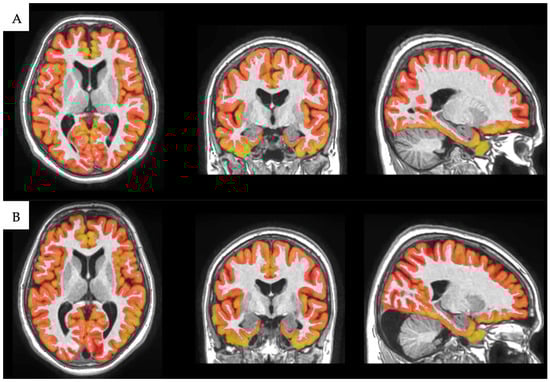

2.3. Image Processing

Volumetric Analysis with volBrain